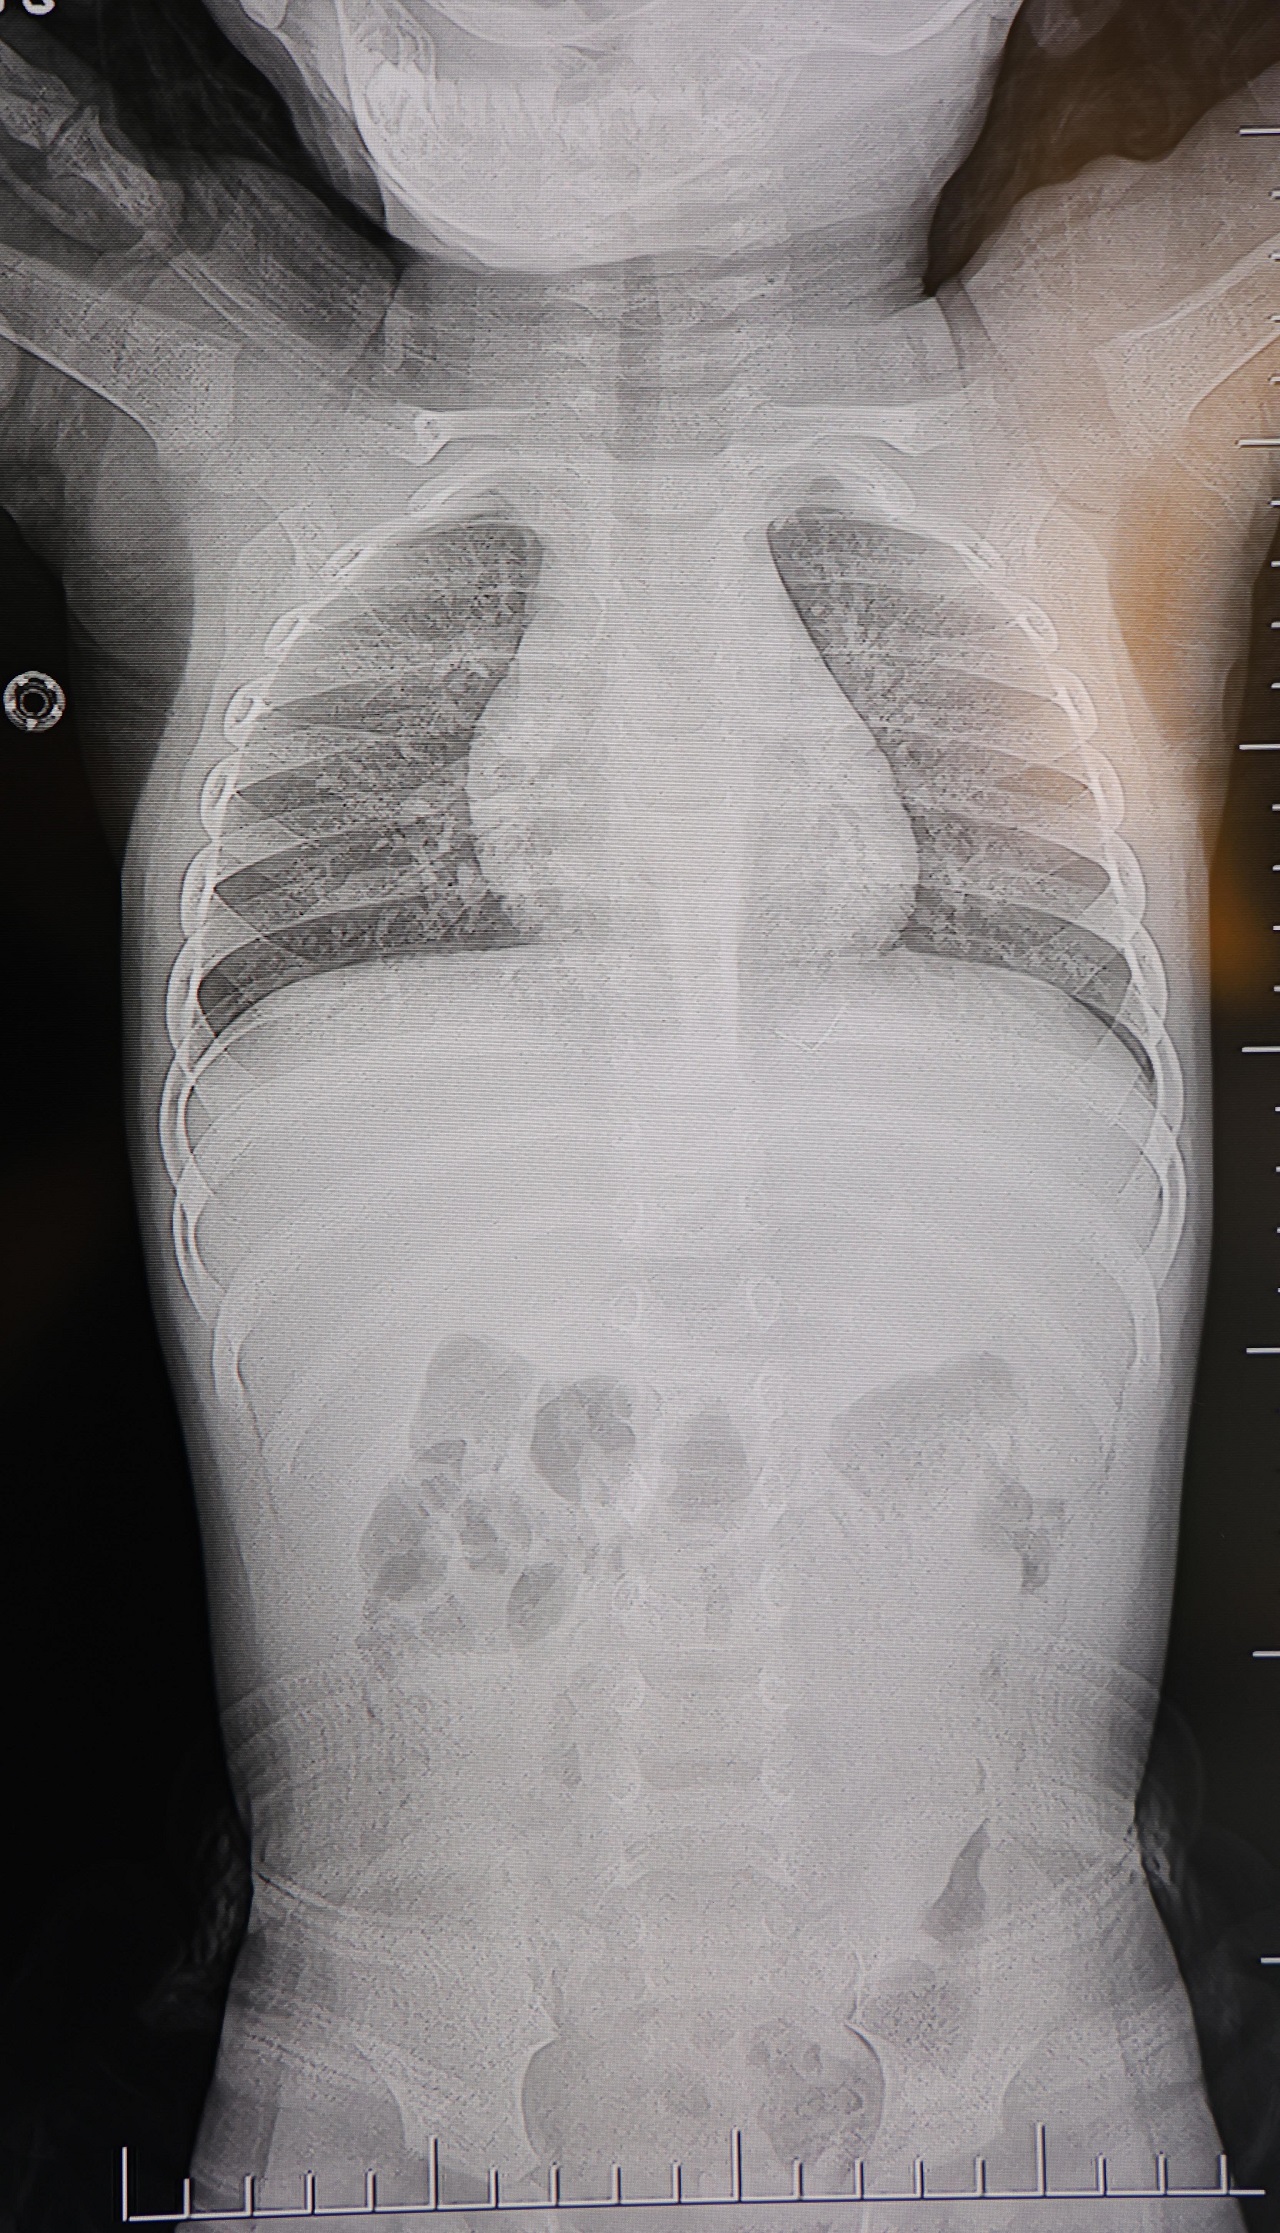

TEL, OMURİLİK KANALINA YAKIN VE AKCİĞER ZARINA DAYANIYORDU

Prof. Dr. Altun’un değerlendirmelerine göre, söz konusu metal tel; bebeğin omurilik kanalına çok yakın, akciğer zarına doğru ilerleyen bir noktadaydı. Bu bölgede gelişebilecek enfeksiyonun hayati risk taşıyabileceği, hatta ilerleyen yaşlarda ciddi omurilik hasarlarına neden olabileceği bildirildi.

“Hastayı tamamen uyutmadan, lokal anestezi ve sedasyon altında müdahale ettik. Cilt altından çıkarılan yabancı cisim yaklaşık 2 santimetre uzunluğunda, zımba teline benzer bir metal parçaydı. Bu tel alınmasaydı, enfeksiyon, omurilik hasarı, akciğere batma ve hatta tümör benzeri reaksiyonlara yol açabilirdi” dedi.